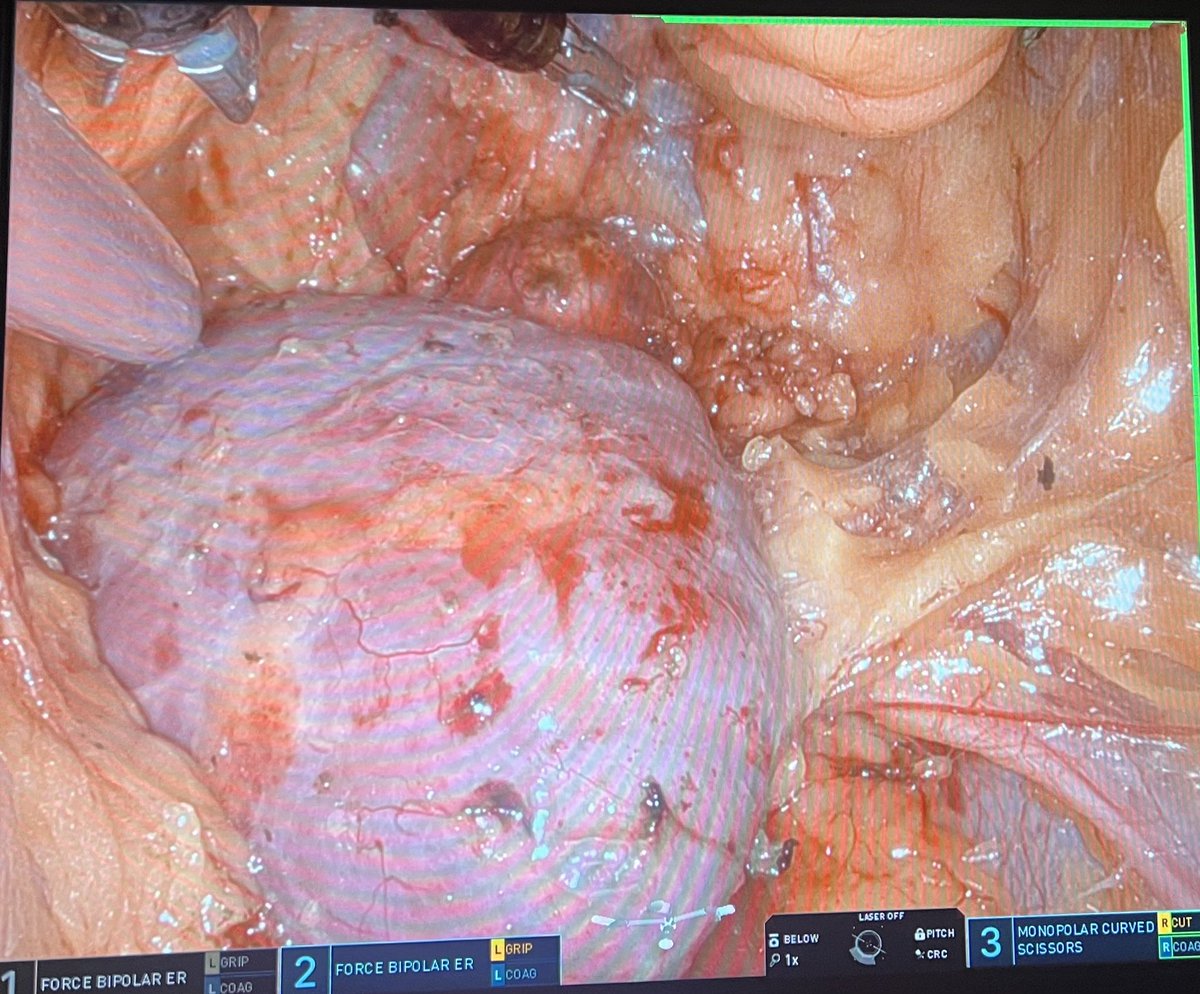

Great presentation by @RyanNelson762 demonstrating how to control bleeding calmly and identifying important studies which highlight the safety of SP partial nephrectomy compared with MP but do confer slightly longer ischemic times. @Endo_Society @SocietySURS @uretericbud